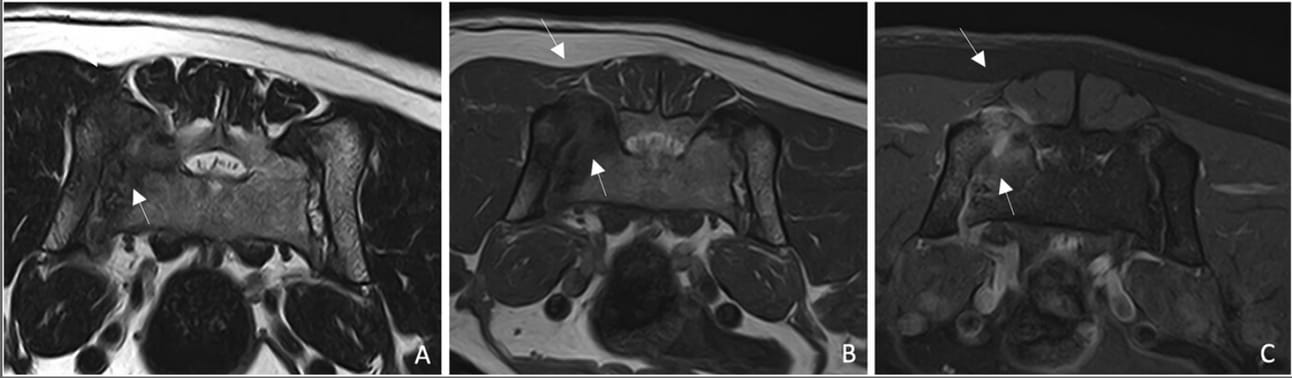

Transverse MRI images of the sacroiliac joints showing the polyostotic lesion previously described. A, B, The lesion is hypointense on T2 W and T1W. C, These changes show moderate heterogeneous contrast enhancement on T1 W Fat Sat postcontrast (C) (white arrows).

MRI identified a polyostotic lesion centered in the right SIJ, affecting the sacral wing and ipsilateral ilium. The lesion was hyperintense on STIR and hypointense on T1W and T2W, with moderate contrast enhancement. Soft tissue thickening and muscle atrophy were noted. Cytology revealed a mixed inflammatory response with lymphocytes, plasma cells, and neutrophils. Histopathology confirmed mild neutrophilic and lymphoplasmacytic osteomyelitis, ruling out neoplasia or infection. Symptomatic treatment with NSAIDs and strict rest led to clinical improvement within six weeks. However, four months later, the dog developed metastatic lymphadenopathy from an undiagnosed primary carcinoma or adenocarcinoma, leading to euthanasia.